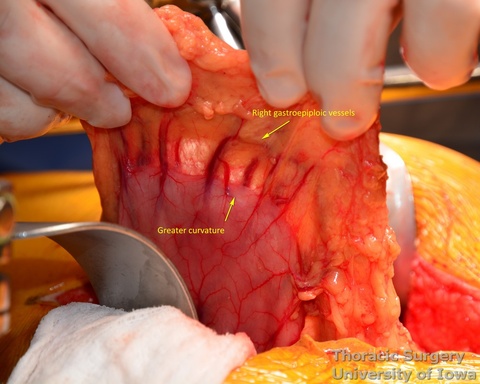

- Procced with mobilization of the stomach. The course of the right gastroepiploic artery is determined.

- The gastrocolic ligament is incised in its avascular portion between the terminal branches of the right and left gastroepiploic vessels, and the lesser sac is entered.

- The greater curvature of the stomach is then mobilized towards the pylorus, dividing the gastrocolic ligament no closer to than 1.5–2 cm to the right gastroepiploic vessels, while protecting the vessels with the fingers of the retracting hand. In morbidly obese patients the right gastroepiploic artery may not be visible or palpable. A Doppler probe is used then to identify its course and origin from the gastroduodenal artery.